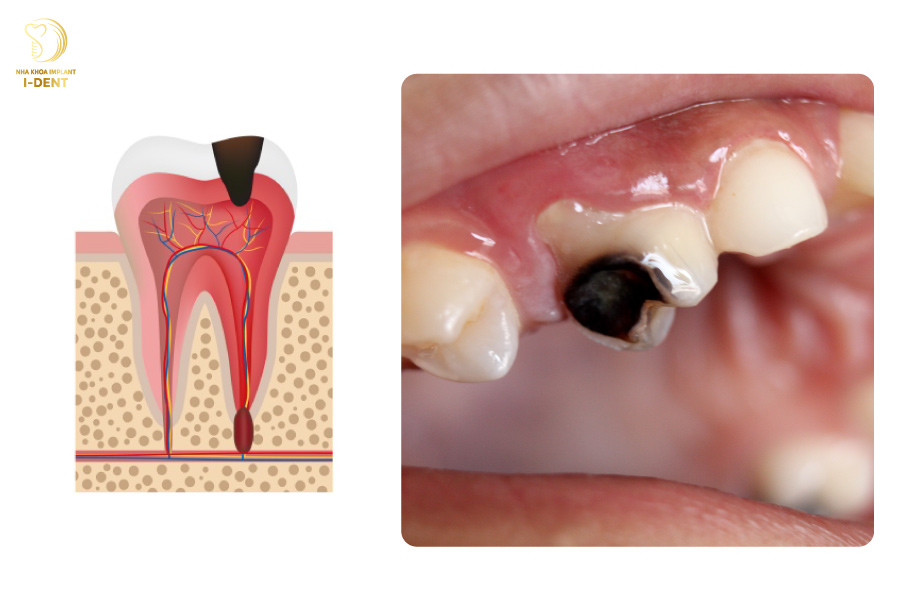

3.4 Giai đoạn 4: Viêm tủy răng

Viêm tủy răng là một trong các giai đoạn sâu răng nguy hiểm nhất vì tủy răng chứa dây thần kinh và mạch máu vận chuyển dinh dưỡng giúp nuôi dưỡng răng. Lỗ sâu răng mở rộng, vi khuẩn tiến dần đến tủy khiến tủy bị tổn thương, sưng to lên và gây đau dữ dội dù không chịu tác động gì. Vùng nướu xung quanh răng dễ bị sưng đỏ và các đốm màu nâu sẫm trước đó chuyển sang màu sẫm hơn hoặc đen.

Giai đoạn 4: Viêm tủy răng: Tủy răng đã bị viêm, vùng nướu xung quanh răng dễ bị sưng đỏ.